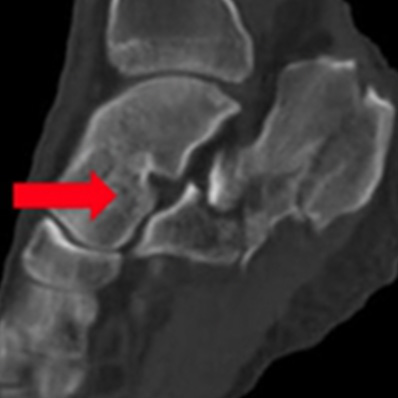

Pylon骨折

踵骨骨折